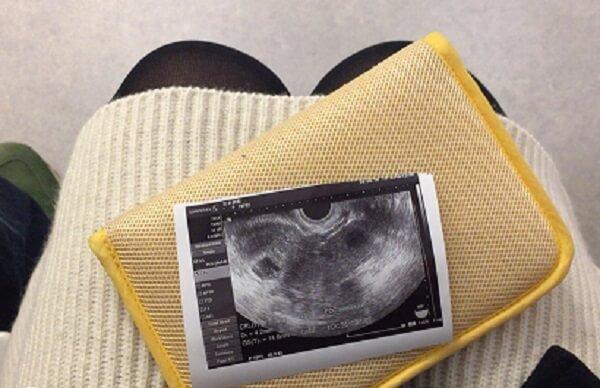

进入怀孕第6周后,在你的子宫里,胚胎正在迅速地成长,现在他大概有小扁豆粒般大小(4~5 毫米长)。宝宝的心脏已经开始划分心室,并进行有规律的跳动及开始供血。这周的细胞还在迅速地分裂,主要器官包括肾和心脏的雏形都已开始发育,神经管开始连接大脑和脊髓,原肠也开始发育。

胚胎的上面和下面开始长出肢体的幼芽,这是将来宝宝的手臂和腿。日后将形成嘴巴的地方的下部,有一些小皱痕,它最终会发育成脖子和下颌。面部的基本器官开始成形,已经能清晰地看到鼻孔,眼睛的雏形也已经具备……生命之初,令人惊叹。